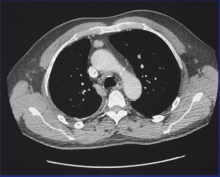

Paul E. Van Schil of Antwerp University Hospital in Belgium presents a discussion on the current status of the management of mesothelioma. He focuses on potentially resectable mesothelioma disease using the surgical techniques of pleurectomy, decortication, and extrapleural pneumonectomy, as well as multimodality therapy.